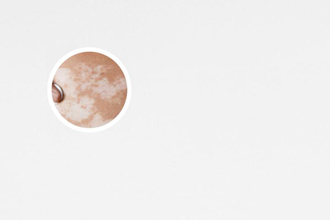

白癜風(fēng),給患者帶來(lái)了很多困擾。在治療白癜風(fēng)的過(guò)程中,311操作流程和注意事項(xiàng)是非常重要的。下面將從不同的維度來(lái)討論這些操作流程和注意事項(xiàng),幫助患者更好地應(yīng)對(duì)白癜風(fēng)。

311操作流程主要包括三個(gè)步驟:前處理、治療和后處理。前處理主要是準(zhǔn)備工作,包括清潔皮膚表面、保護(hù)周圍健康皮膚、確定治療區(qū)域等。治療階段使用的是UVA波長(zhǎng)為311nm的燈光照射,這種波長(zhǎng)的光線能夠滲透到皮膚的深層,達(dá)到治療結(jié)果。治療時(shí)間根據(jù)病情的輕重以及病人的耐受程度而定,通常每次治療時(shí)間在幾分鐘至十幾分鐘之間。治療結(jié)束后,還需要進(jìn)行后處理工作,包括清潔皮膚、觀察治療后的反應(yīng)等。